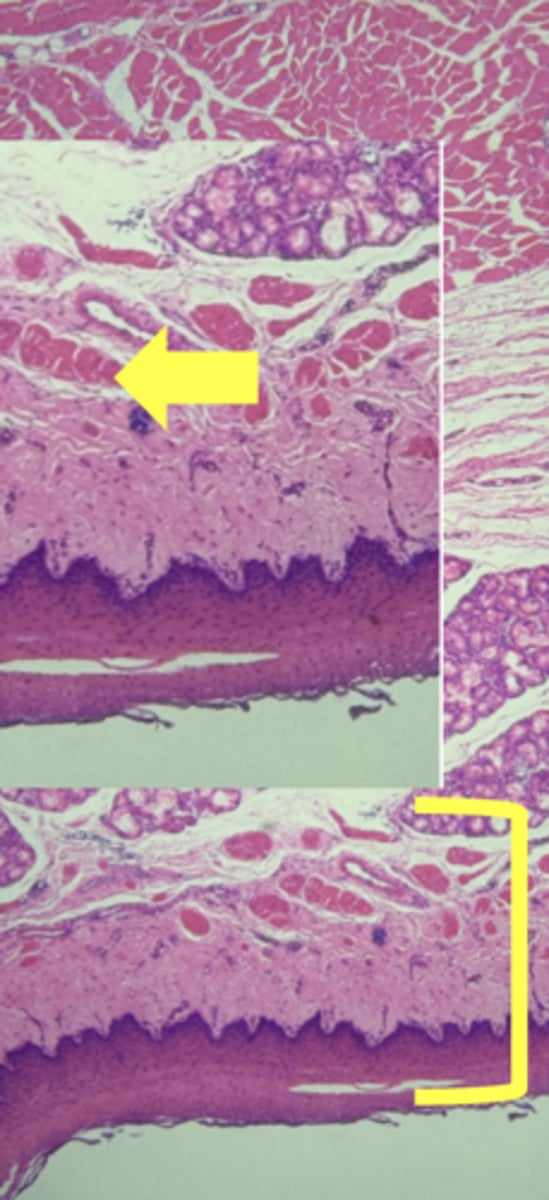

Esophagus

name the tissue

Mucosa

(esophagus)

Submucosa

muscularis externa

stratified squamous epithilium (KEY CHARACTERISTIC)

lamina propria

muscularis mucosae

circular layer

longitudinal layer